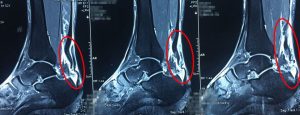

Tối cùng ngày nhập viện, bệnh nhân có chơi đánh quần vợt. Khi đang chơi thì đột ngột đau chói vùng gót chân trái, kèm với đó là tiếng kêu “pop” xuất phát từ vùng tổn thương. Sau chấn thương, bệnh nhận bị hạn chế vận động cổ chân trái, cảm giác bàn chân trái không có lực và được người nhà đưa vào nhập viện tại Bệnh viện Xuyên Á – Vĩnh Long.